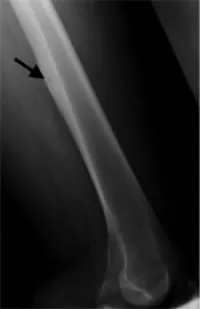

Imaging usually is very typical: X-rays show new bone formation and sometimes a small lucent spot (smaller than 1.5 cm), which is defined as the nidus. Computed tomography (cat scan, CT) is even better suited to show the new bone formation and the nidus. Because there may be a lot of inflammatory swelling and edema in the bone and soft tissues around the tumor magnetic resonance imaging (MRI) may sometimes be difficult to interpret and CT may be required to further assess these tumors. Radionuclide or bone scans show increased uptake of the radioactive tracer, this may sometimes be very focal.

X-ray of an osteoid osteoma of the thigh (femur) with increased bone formation and subtle lucency (arrow).